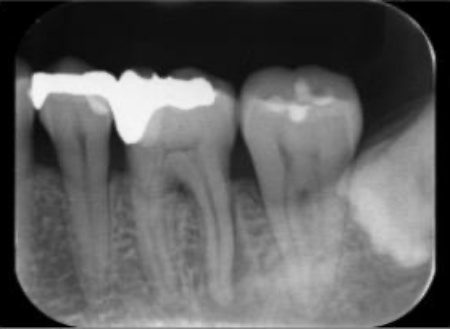

レントゲンを撮影して詳しく調べたところ、歯の奥側の根の先端部分に骨が溶けたことで黒く透けて見える透過像が確認されました。

この透過像は歯の神経や血管が通る管「根管」の内部で細菌感染が起こり、根の先にまで炎症が広がっているサインです。

マイクロスコープを用いて根管の内部を確認したところ、この歯には4本の根管がありました。

最後に、治療後のレントゲンで4本すべての根管に充填材が緊密に行き渡っていること、処置部位に問題がないことを確認して、治療を終了しました。